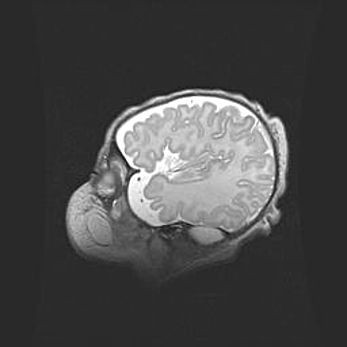

Множественные кисты обоих полушарий головного мозга, наибольшая из них в правой затылочной области. Ассиметричная атрофическая гидроцефалия.

Возраст: 7 месяцев

Вес: 5660 г

Пол: мужской

Окружность головы: 41,5 см

Срок гестации: 28-29 недель

Кисты головного мозга развиваются в результате многоочаговых некрозов вещества мозга и возникают вследствие перенесенной перинатальной инфекции, менингитов, энцефалитов, асфиксии, родовой травмы, расстройств мозгового кровообращения различного генеза. Образованию кист в веществе головного мозга плодов и новорожденных способствуют такие факторы, как высокое содержание в нем воды, недостаточная (или отсутствие) миелинизация и слабая астроглиальная реакция на повреждение.

Кисты могут сочетаться с гидроцефалией и другими поражениями головного мозга.